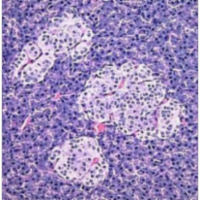

From the hypertext description in this site, the endocrine system is a collection of glands that secrete chemical messages we call hormones. These signals are passed through the blood to arrive at a target organ, which has cells possessing the appropriate receptor. Exocrine glands (not part of the endocrine system) secrete products that are passed outside the body. Sweat glands, salivary glands, and digestive glands are examples of exocrine glands.